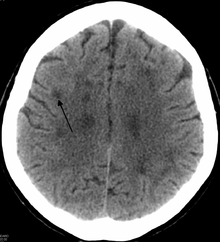

Leukoencephalopathy

The term Leukoencephalopathy is a broad term for leukodystrophy-like diseases.[1] It is applied to all brain white matter diseases, whether their molecular cause is known or not. It can refer specifically to any of these diseases: